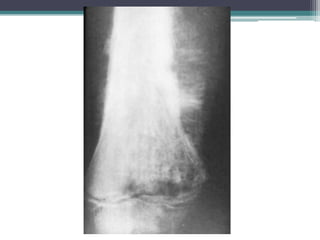

PACIENTE CON CA.

DE MAMA CON

METÁSTASIS

OSTEOBLÁSTICA

QUE PRESENTA

LESIÓN

ESCLERÓTICA

SUTÍL EN LA

METÁFISIS DEL

HÚMERO.

PACIENTE CON CA. DE MAMA CON METÁSTASIS OSTEOBLÁSTICA QUE PRESENTA LESIÓN ESCLERÓTICA SUTÍL EN LA METÁFISIS DEL HÚMERO.